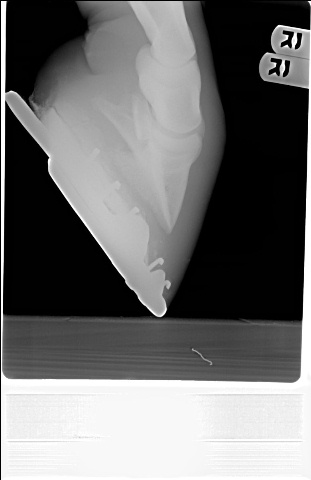

Posted on Wednesday, Apr 27, 2005 - 10:25 am: My horse wasn't cooperating for the rear feet...but here they are

Posted on Tuesday, Jul 19, 2005 - 9:07 pm:  What do you all think? I can't remember when this was taken...but just to give you a before and after. The vet said he has/had severely underslung heels and it was putting pressure on the DDFT - which is he says the most likely cause of my horses' problems. |

Posted on Wednesday, Jul 20, 2005 - 7:36 am: WTG since the radiographs are 2 dimensional and we only have lateral views you cannot evaluate the nails positions with respect to the bone. For instance the nail could be tapped to the outside of the foot and would have the same appearance.Ailleen the angles, distance, and low light make evaluation difficult. Better would be to maintain the distance but to telephoto in just a bit to the point where you get distal cannon, fetlock and hook. Flash or outside with the sun behind you will improve the lighting. Also the closer the camera is to the ground, to avoid foreshortening, the better. DrO |